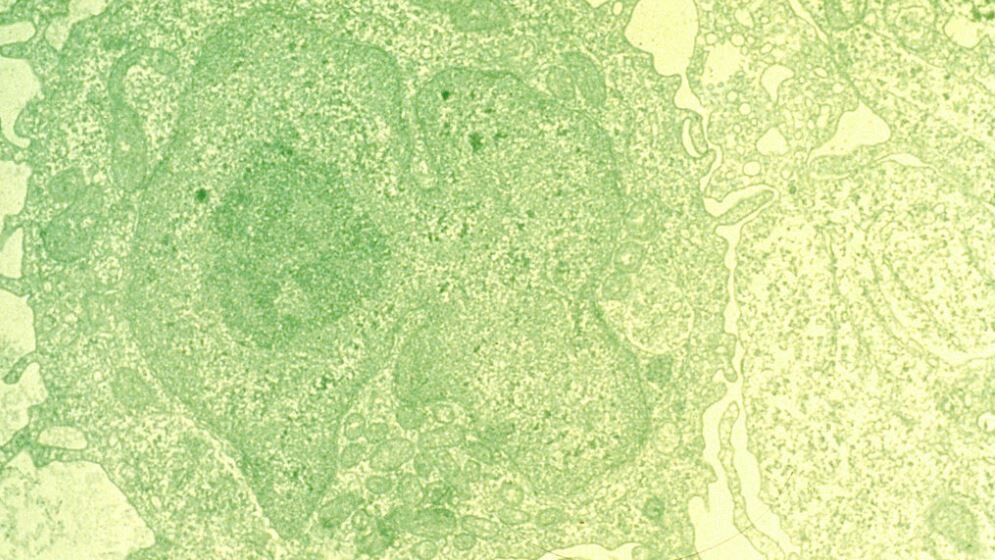

Etwa acht Prozent aller soliden Tumoren zeigen Veränderungen im Erbgut des BRAF-Gens, die als therapeutische Zielstruktur genutzt werden können. Die Mutation des B-Raf-Proteins an der Aminosäureposition 600 aktiviert einen Signalweg besonders stark, der am Wachstum und Überleben von Zellen beteiligt ist. Dies kann in Kombination mit weiteren Mutationen zu unkontrolliertem Zellwachstum und somit der Entstehung von Krebs führen. Fast 50 Prozent aller fortgeschrittenen Melanome, dem schwarzen Hautkrebs, besitzen eine Mutation im BRAF-Gen. Bei diesen Patienten setzen Ärzte den spezifischen BRAF-Hemmer Vemurafenib bereits ein. Bei der Haarzell-Leukämie (HCL) – ihr Name leitet sich von dem charakteristischen Aussehen der Zellausläufer der Krebszellen ab – liegen bei 95-100 Prozent aller Erkrankten ebenfalls Mutationen des BRAF-Gens vor. Auch hier wird Vemurafenib als zielgerichtete Therapie gegen das fehlerhaft aktivierte B-Raf-Protein als Behandlungsoption verwendet.